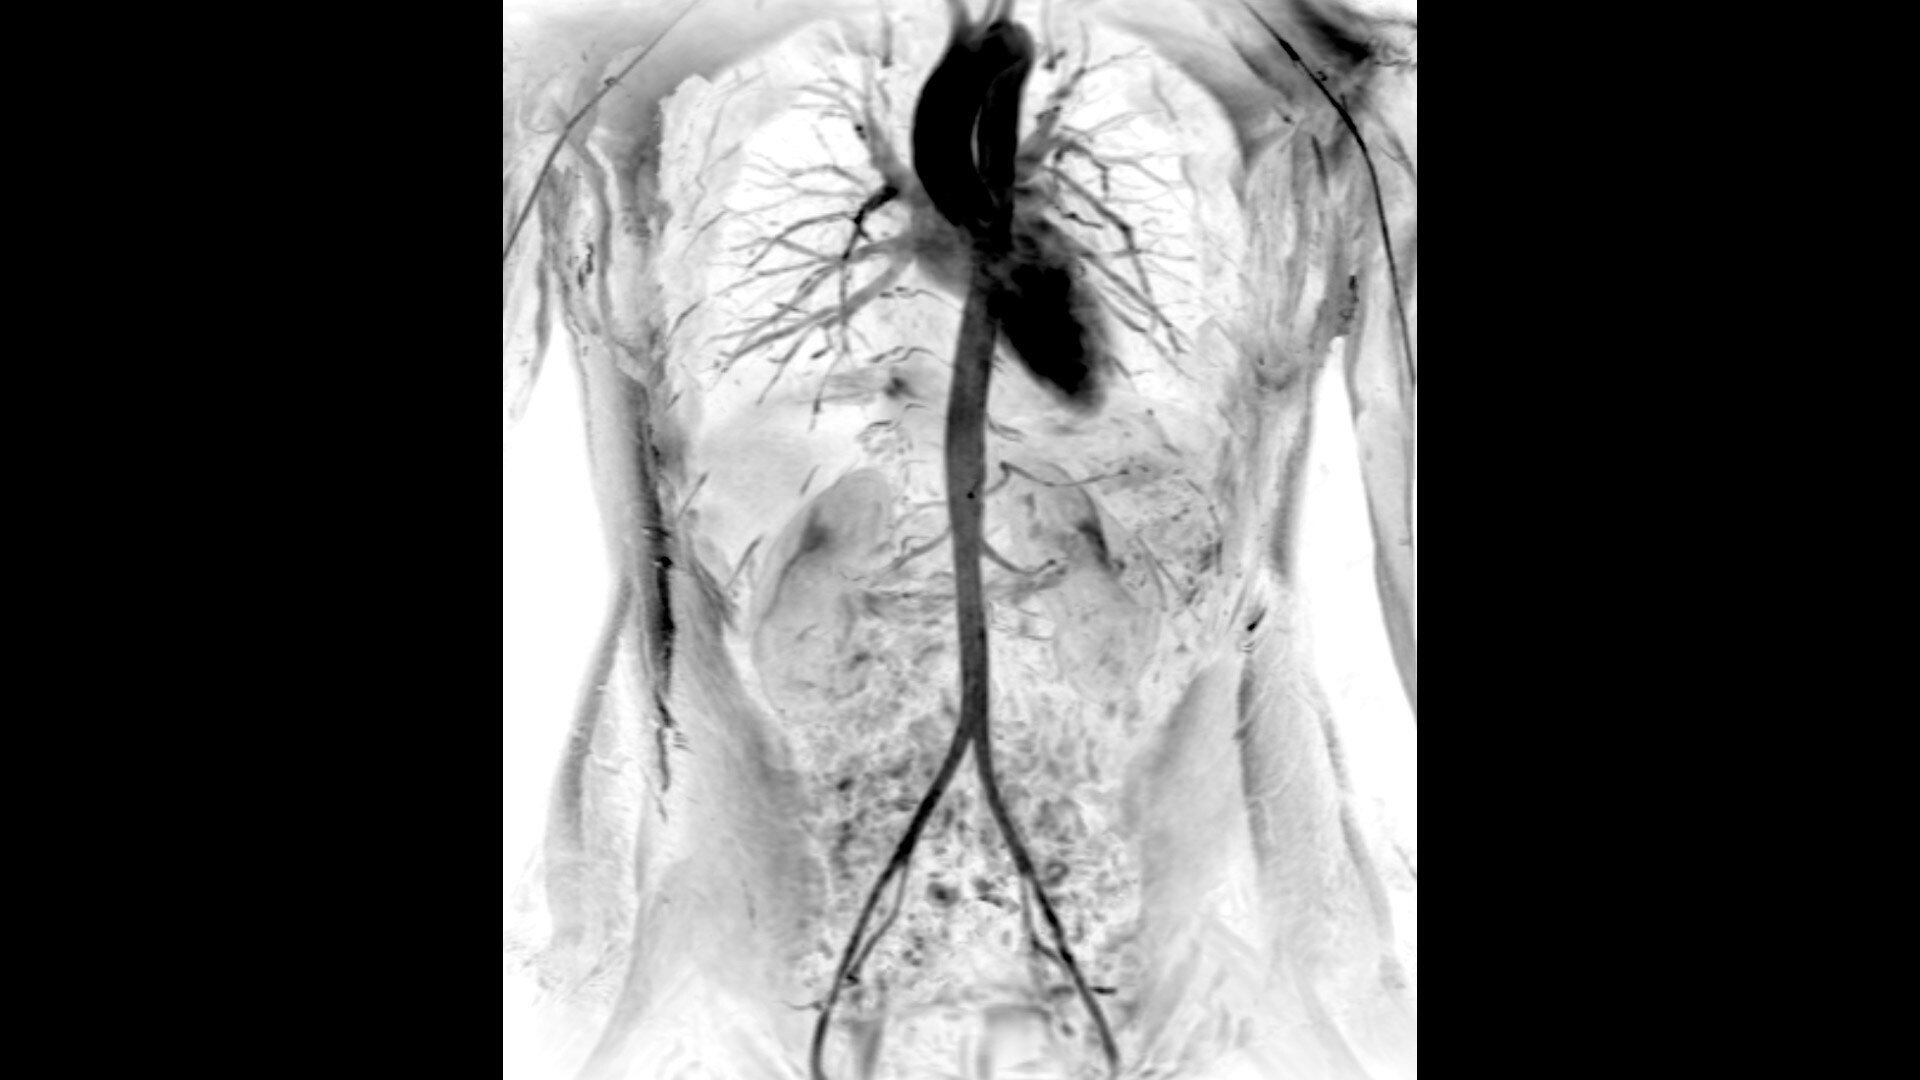

An award-winning industry first in MRI coils. With overlapping, ultra-light, flexible coil elements at their heart, AIR™ Coils deliver an MRI experience that gets closer to your patient, so you get closer to the truth. Representing a new standard in MRI coil technology, AIR™ Coils enable a simplified, faster workflow while maintaining excellent image quality. Scan complex anatomies and complicated conditions in a variety of patient sizes with exceptional results.

The shape of the MRI coil no longer determines what you can do with it. Wrap it around a knee for a complete knee image. Drape it over the patient's body. With an adaptive AIR™ Coil that is light, form fitting and easy to position, it’s the closest you can get to total positioning freedom with 360-degree coverage.

• Highest channel count and coverage in the industry

• Space-saving design